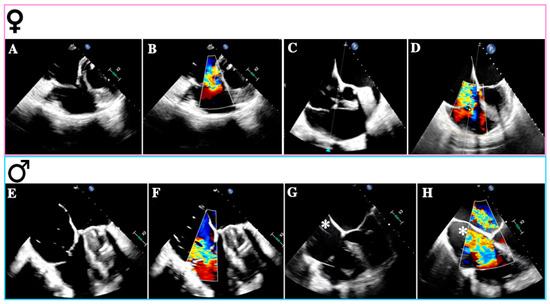

- Gual-Capllonch, F.; Cediel, G.; Ferrer, E.; Teis, A.; Juncà, G.; Vallejo, N.; López-Ayerbe, J.; Bayes-Genis, A. Sex-Related Differences in the Mechanism of Functional Tricuspid Regurgitation. Heart Lung Circ. 2021, 30, e16–e22. [Google Scholar] [CrossRef]